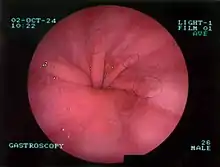

- Fibroscopie œsogastrique : visualise la hernie hiatale, observation d'érosion et d'ulcération si reflux gastro-œsophagien.